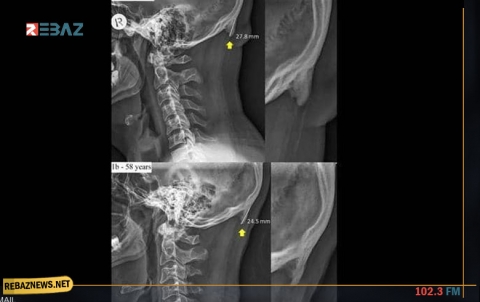

يقول العلم إنه كلما تقدم الإنسان في العمر، أصبحت عظامه أكثر رقة وأقل كثافة، الأمر الذي يجعلها عرضة لأمراض عدة،...